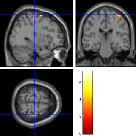

Once the reduced FOV images are available, the proposed pMRI 4D-UWR-SENSE algorithm and its early UWR-SENSE version have been utilized in a final step to reconstruct the full FOV EPI images and compared to the mSENSE Siemens solution. For the wavelet-based regularization, dyadic Symmlet orthonormal wavelet bases [48] associated with filters of length 8 have been used over resolution levels. The reconstructed EPI images then enter in our fMRI study in order to measure the impact of the reconstruction method choice on brain activity detection. Note also that the proposed reconstruction algorithm requires the estimation of the coil sensitivity maps (matrix in Eq. (2)). As proposed in [4], the latter were estimated by dividing the coil-specific images by the module of the Sum Of Squares (SOS) images, which are computed from the specific acquisition of the -space centre (24 lines) before the scans. The same sensitivity map estimation is then used for all the compared methods. Fig. 5 compares the two pMRI reconstruction algorithms to illustrate on axial, coronal and sagittal EPI slices how the mSENSE reconstruction artifacts have been removed using the 4D-UWR-SENSE approach. Reconstructed mSENSE images actually present large artifacts located both at the centre and boundaries of the brain in sensory and cognitive regions (temporal lobes, frontal and motor cortices, …). This results in SNR loss and thus may have a dramatic impact for activation detection in these brain regions. Note that these conclusions are reproducible across subjects although the artifacts may appear on different slices (see red circles in Fig. 5). One can also notice that some residual artifacts still exist in the reconstructed images with our pipeline especially for . Such strong artifacts are only attenuated and not fully removed because of the high level of information loss at .

| mSENSE | 4D-UWR-SENSE | ||

| Axial |  |

|

|

| Coronal | |||

| Sagittal | |||

| Axial |  |

|

|

| Coronal | |||

| Sagittal |